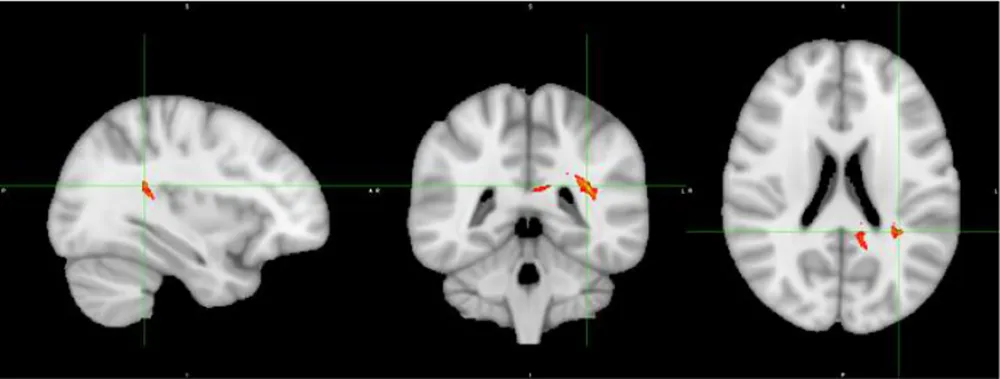

In terms of inhibitory control and ADHD severity, we found that poorer inhibitory control (i.e. slower SSRTs) correlated with the degree of hyperactivity-impulsivity SWAN scale score (r= .38, p=.007), rather than the inattention score (r=0.19, p=.17). This finding subsequently led us to correlate white matter changes in our Table 3’s tracts of interest with hyperactivity severity and found that radial diffusivity (RD) in IFOF white matter between IFG and STG correlated with hyperactivity-impulsivity scores (r = 0.45, p=0.002, uncorrected), displayed in Figure 2. Because age did correlate with the hyperactivity measure and thus represented a potential confounder (r= -0.38, p=.007), a linear regression was performed to test the impact of age onto the correlation between RD and hyperactivity, and showed no impact.

Figure 2

Severity of ADHD symptoms versus white matter disruption within fronto-temporal IFOF.

In terms of inhibitory control and white matter changes detailed in Table 3, there was one correlation between RD within IFG to STG (IFOF) white matter and SSRT (r=0.26, p=.073, uncorrected), displayed in Figure 3, which represented a replication from the previous pilot study, discussed later. There was no correlation between age and RD within this tract.

Figure 3

Inhibitory control versus white matter disruption in fronto-temporal IFOF.